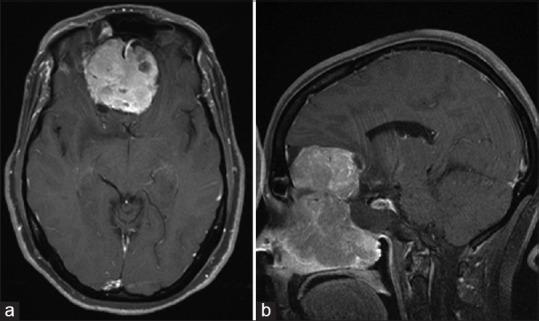

Esthesioneuroblastoma is a locally aggressive cancer of the nasal cavity. While systemic metastasis can occur in 10-30% of patients, there are only six reported cases of distal metastasis from leptomeningeal dissemination.

The authors report two cases of esthesioneuroblastoma treated previously with multimodal therapy in which distal metastatic recurrence was found and describe their treatment protocol, which has resulted in long-term success.

嗅神经母细胞瘤是鼻腔的一种局部侵袭性癌症。虽然10% - 30%的患者可能发生全身转移,但仅有6例经软脑膜播散导致远处转移的报道。

作者报告了2例先前接受多模式治疗的嗅神经母细胞瘤病例,其中发现了远处转移性复发,并描述了他们的治疗方案,该方案已取得长期成功。